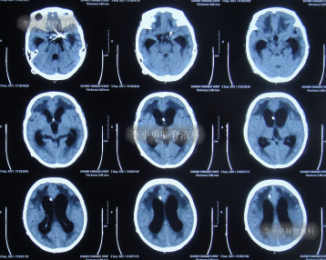

引流是基础,但战胜感染、改善患者全身状况才是康复的关键。在持续引流的同时,团队根据药敏结果使用敏感抗生素,并辅以营养神经、维持水电解质平衡、强化肺部分泌物引流等综合支持治疗。在医护人员的精心照料下,患者的体温逐渐恢复正常,意识从昏迷转为清醒,肺部感染也被有效控制。经过长达76天的精心准备,患者脑室缩小,颅内压力稳定,全身感染征象完全消失。此时,植入新分流管的最佳时机已然成熟。李小勇主任团队为患者成功实施了新的脑室腹腔分流术。这一次,分流系统在清洁、稳定的环境中开始正常工作。

术后,患者恢复顺利。入院时嗜睡发热、偏瘫在床的她,出院时已能清晰地与家人交流,自己吃饭,肢体活动明显改善。更令人欣喜的是,在出院近半年后的随访中,家属反馈患者已能在助行器辅助下站立、行走,生活基本实现自理。